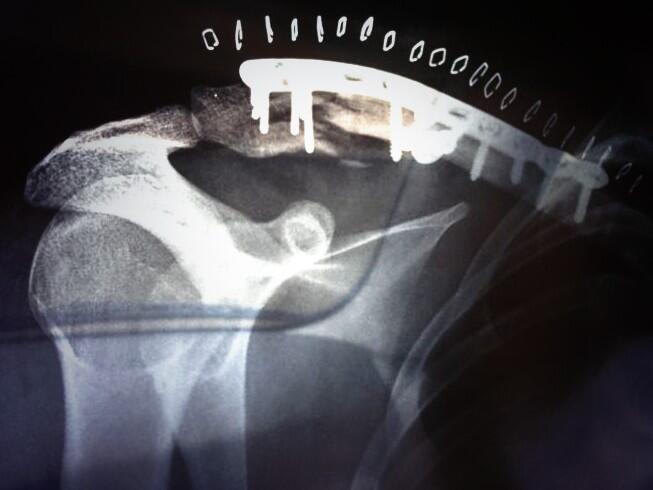

Efrén Vázquez fue intervenido ayer de la fractura de su clavícula derecha ocasionada por una caída durante la primera jornada de entrenamientos del Gran Premio de Francia, en una operación exitosa. La intervención se ha llevado a cabo por el doctor Xavier Mir en el Hospital Universitario Quirón Dexeus de Barcelona y ha consistido en la sustitución de la placa metálica que Efrentxu llevaba en su hombro derecho desde una intervención en 2006 por una más grande y fijada con más clavos.

“La dificultad es que ha sido una fractura que se ha provocado en donde ya había una placa de una antigua lesión y esto ha provocado que la placa hiciera de brazo de palanca y hay un fragmento de la clavícula muy grande y otro muy pequeño, y además el pequeño tiene varios pequeños fragmentos. Esta es la principal dificultad”, expresó el doctor Mir después de pasar por el quirófano.

"En principio estamos muy contentos de la estabilidad de la placa que hemos puesto, pero hay que ver cómo evoluciona, primero 48 horas en reposo, prácticamente absoluto. A partir de las 48 horas nos pondremos en contacto con sus fisioterapeutas y empezaremos un protocolo de rehabilitación de momento en descarga, sin peso, y a partir de aquí iremos avanzando más”, añadió Xavier Mir, que abogaba por la prudencia, a la espera de la sucesión de las primera horas después de la operación.